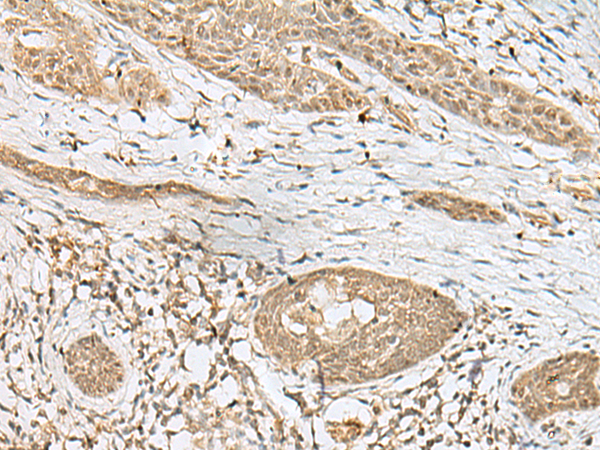

分类: 科研抗体货号: P09961别名: TGC1; TSGA3; SPGFX2应用: IHC反应种属: Human